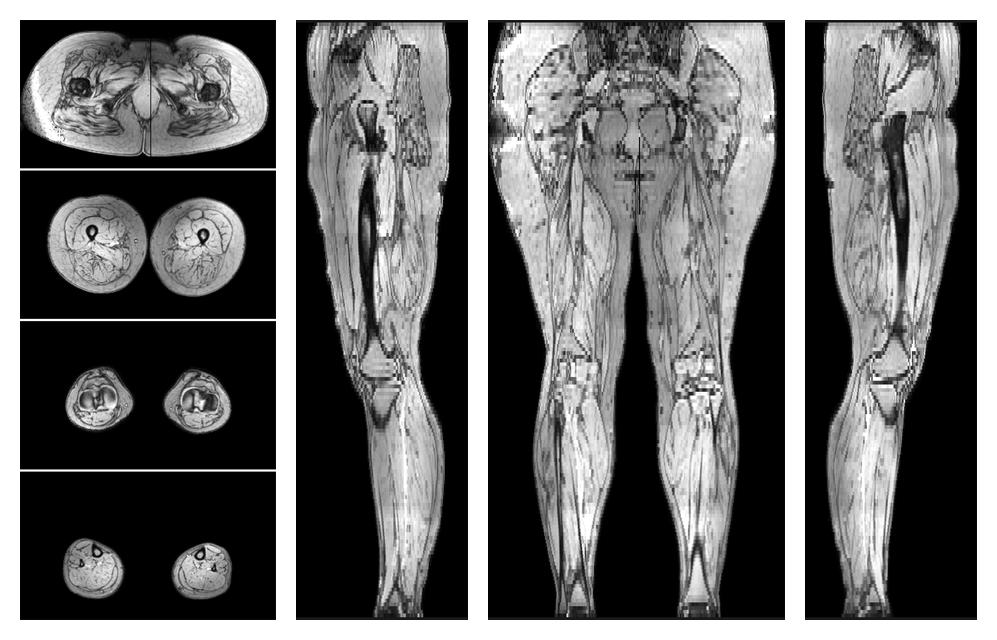

• Out phase image

The out-phase image of the dixon reconstruction for water fat quantification.